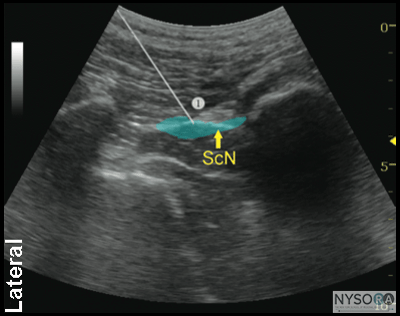

Figure 2-4: Transgluteal approach to sciatic block; patient position, transducer (curved) placement and needle insertion. Distribution of Blockade Sciatic nerve block results in anesthesia of the entire lower limb below the knee, both motor and sensory blockade, with the exception of a variable strip of skin on the medial leg and foot, which is the territory of the saphenous nerve, a branch of the femoral nerve. In addition, both the transgluteal and subgluteal approaches provide motor blockade of the hamstring muscles. The skin of the posterior aspect of the thigh however, is supplied by the posterior cutaneous nerve of the thigh, which has its origin from the sciatic nerve more proximal than the subgluteal approach. It is, therefore, unreliably anesthetized with subgluteal block; however, it is of relatively little clinical importance. ![]() Figure 2-5: Sciatic nerve (yellow arrows) as seen in the subgluteal position (linear transducer), needle path (white arrows) and local anesthetic (turquoise arrows) in the intramuscular tunnel surrounding the sciatic nerve. Equipment Equipment needed is as follows:

Technique The description of the technique in this chapter will focus primarily on the transgluteal approach. However, since the subgluteal approach is performed just a few centimeters more distal and it is technically easier, the reader can easily perform either approach by using general guidelines provided and referring to Figure 2-3, Figure 2-4, and algorithms at the end of the chapter. With the patient in the described position, the skin is disinfected and the transducer is positioned so as to identify the sciatic nerve (Figure 2-4). If the nerve is not immediately apparent, tilting the transducer proximally or distally can help improve the contrast and bring the nerve “out” of the background of the musculature. Often, the nerve is much better imaged after the injection of local anesthetic (Figure 2-5). Alternatively, sliding the transducer slightly proximally or distally can improve the quality of the image and allow for better visualization. Once identified, the needle is inserted in-plane, typically from the lateral aspect of the transducer and advanced toward the sciatic nerve. If nerve stimulation is used (1.0 mA, 0.1 msec), the passage of the needle through the anterior fascial plane of the gluteus muscles often is associated with a motor response of the calf or foot. Once the needle tip is positioned adjacent to the nerve (Figure 2-6A) and after careful aspiration to rule out an intravascular needle placement, 1 to 2 mL of local anesthetic is injected to document the proper injection site. Such injection often displaces the sciatic nerve away from the needle; therefore, an additional advancement of the needle 1 to 2 mm toward the nerve may be necessary to ensure the proper spread of the local anesthetic. When injection of the local anesthetic does not appear to result in a spread around the sciatic nerve, additional needle repositions and injections may be necessary. Assuring the absence of high resistance to injection is of utmost importance because the needle tip is difficult to visualize on ultrasound due to the steep angle and depth of the needle placement.

Figure 2-6: (A) Ultrasound image demonstrating the simulated needle path to reach the sciatic nerve (ScN) using an in-plane technique in transgluteal approach. The simulated needle (1) is shown transversing the gluteus muscle with its tip positioned at the lateral aspect of the sciatic nerve. (B) Needle path and distribution of local anesthetic (blue shaded area) to block the ScN through the transgluteal approach. In an adult patient, 15 to 20 mL of local anesthetic is usually adequate for successful blockade of sciatic nerve (Figure 2-6). Although a single injection of such volumes of local anesthetic suffices, it may be beneficial to inject two to three smaller aliquots at different locations to ensure the spread of the local anesthetic solution around the sciatic nerve.